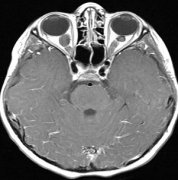

脑干胶质瘤分为两种:弥漫性脑干胶质瘤(最常见于桥脑)和局灶性脑干胶质瘤(大多位于中脑和延髓),下面我们分享一例脑干胶质瘤德国成功手术案例,前言:我庆幸,各种努...

●弥漫性内生性桥脑胶质瘤(Diffuse intrinsic pontine gliomas)是罕见的、频繁见于年轻儿童的脑瘤,平均发病年龄是5~9岁。 ●几乎80%的弥漫性内生性桥脑胶质瘤的活检结果发现组蛋...